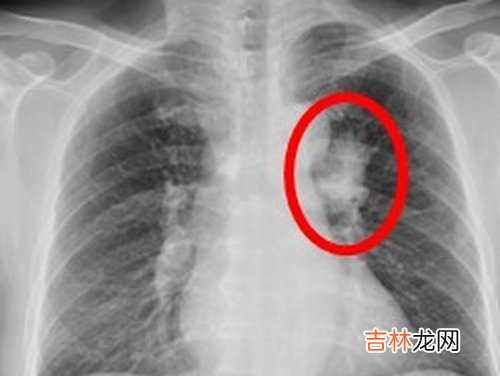

x线可诱发癌症

放射诊断检查是一把双刃剑 。一方面,影像能清晰地分辨出病因,是重要的诊断和治疗方法;另一方面,它对人体是有伤害的,即它可能诱发癌症 。可人们似乎对此并没有重视 。

【X线可诱发癌症滥用成最严重医源性放射损伤】 牛津大学和英国癌症研究中心的科学家在对15个工业国家的统计数据分析研究后发现,英国每年诊断出的癌症病例中有0.6%是由x线检查所致;在德国,1.5%的癌症患者是由x线导致的;在x线和ct检查更为普遍的日本,每年新增癌症病例中有3.2%是由这两项检查造成的 。